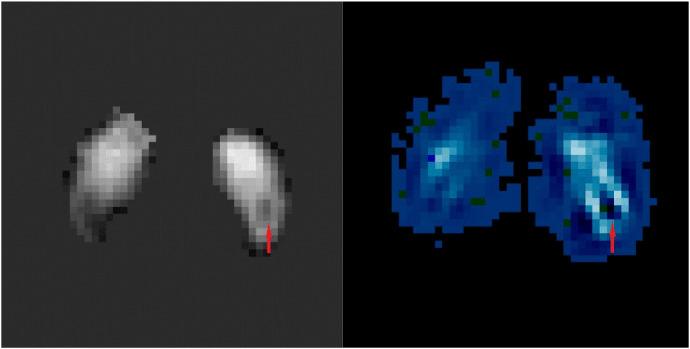

基于定量磁化率映射的混合特征提取用于帕金森病的诊断。

Quantitative susceptibility mapping based hybrid feature extraction for diagnosis of Parkinson's disease.

Parkinson's disease is the second most common neurodegenerative disease in the elderly after Alzheimer's disease. The aetiology and pathogenesis of Parkinson's disease (PD) are still unclear, but the loss of dopaminergic cells and the excessive iron deposition in the substantia nigra (SN) are associated with the pathophysiology. As an imaging technique that can quantitatively reflect the amount of iron deposition, Quantitative Susceptibility Mapping (QSM) has been shown to be a promising modality for the diagnosis of PD. In the present work, we propose a hybrid feature extraction method for PD diagnosis using QSM images. First, we extract radiomics features from the SN using QSM and employ machine learning algorithms to classify PD and normal controls (NC). This approach allows us to investigate which features are most vulnerable to the effects of the disease. Along with this approach, we propose a Convolutional Neural Network (CNN) based method which can extract different features from the QSM image to further support the diagnosis of PD. Finally, we combine these two types of features and we find that the radiomics features and CNN features are complementary to each other, which helps further improve the classification (diagnostic) performance. We conclude that: (1) radiomics features from QSM data have significant clinical value for the diagnosis of PD; (2) CNN features are also useful in the diagnosis of PD; and (3) the combination of radiomics features and CNN features can enhance the diagnostic accuracy.

帕金森病是仅次于阿尔茨海默病的老年人第二常见的神经退行性疾病。帕金森病(PD)的病因和发病机制尚不清楚,但黑质(SN)中多巴胺能细胞的丧失和过量的铁沉积与病理生理学有关。作为一种可以定量反映铁沉积量的成像技术,定量磁敏感图(QSM)已被证明是诊断 PD 的一种很有前途的方法。在本工作中,我们提出了一种使用 QSM 图像进行 PD 诊断的混合特征提取方法。首先,我们从 SN 中提取 QSM 图像的放射组学特征,并使用机器学习算法对 PD 和正常对照(NC)进行分类。这种方法可以让我们研究哪些特征对疾病的影响最敏感。除了这种方法,我们还提出了一种基于卷积神经网络(CNN)的方法,该方法可以从 QSM 图像中提取不同的特征,以进一步支持 PD 的诊断。最后,我们将这两种类型的特征结合起来,发现放射组学特征和 CNN 特征是互补的,这有助于进一步提高分类(诊断)性能。我们得出结论:(1)来自 QSM 数据的放射组学特征对 PD 的诊断具有重要的临床价值;(2)CNN 特征在 PD 诊断中也很有用;(3)放射组学特征和 CNN 特征的结合可以提高诊断准确性。